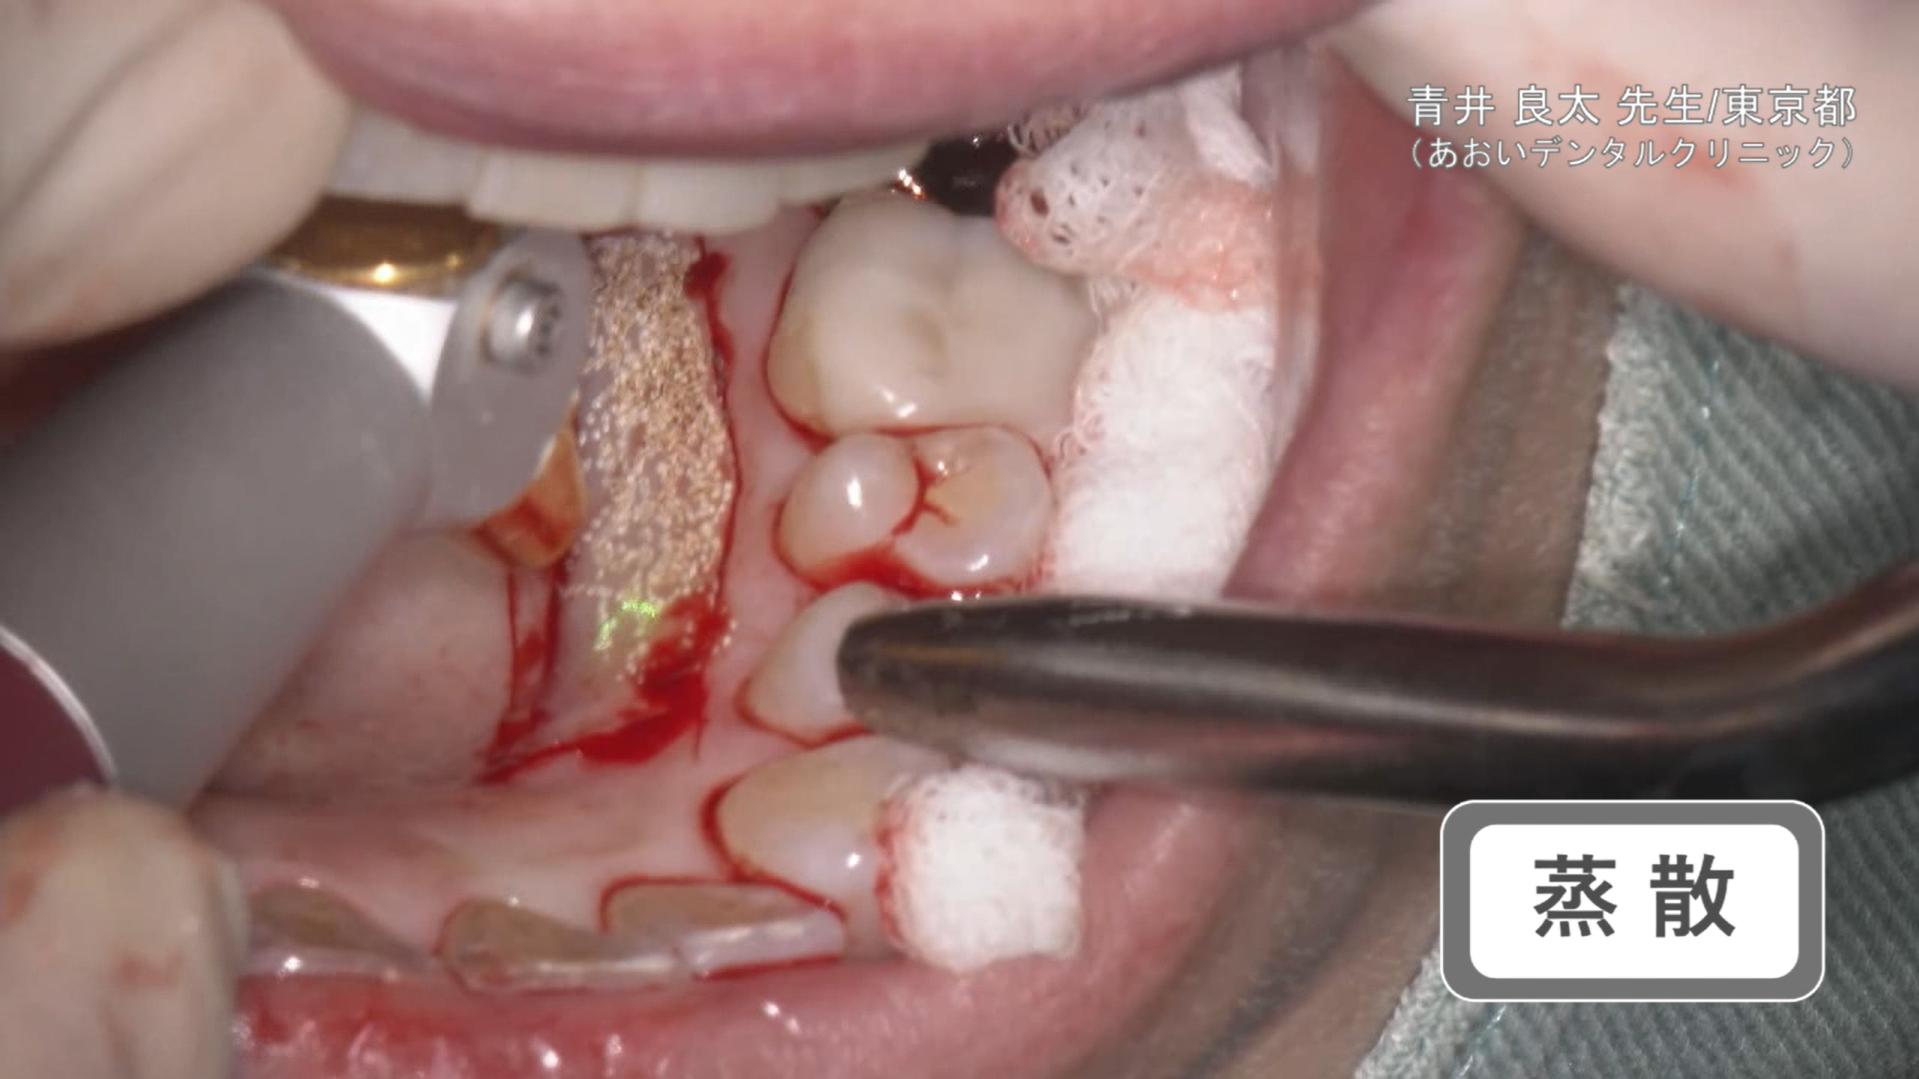

蒸散

臨床例:注水型炭酸ガスレーザーNEOS(最大出力25W)を使用した先生の臨床例です。